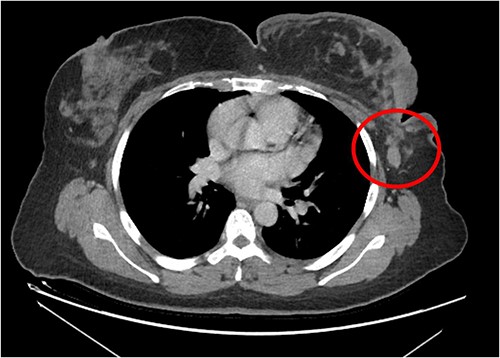

The patient received a total of six cycles of IA protocol, one cycle of goserelin as a means of fertility preservation, with remarkable clinical improvement, she stopped her morphine tablets (both long-duration and as needed) after the third cycle as her pain resolved, kept only on pregabalin. The mass shrunk remarkably as shown in Fig. 5.

She underwent positron emission tomography/computed tomography after the sixth cycle, shown in Fig. 6. It showed a left breast hypermetabolic mass, compatible with known primary disease, there was no previous study for comparison, however, comparison with previous CT showed marked interval morphological regression of the tumor, no hypermetabolic lymph nodes, with no distant metastasis. Follow up breast ultrasound showed multifocal multicentric left breast lesions with few suspicious left axillary lymph nodes. The patient was seen in the surgical oncology outpatient clinic and prepared for mastectomy.

Hypermetabolic left breast mass in last positron emission tomography/computed tomography, following six cycles of IA.